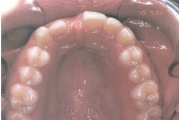

Kaasasündinud hammaste puudumine

Sagedamini puuduvad hambad: teised premolaarid, ülemised lateraalsed intsisiivid, alumised tsentraalsed intsisiivid.